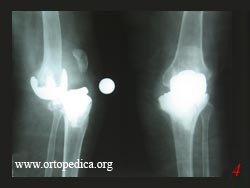

Пример №6 Ревизионное эндопротезирование коленного сустава

1. Состояние после первичного тотального эндопротезирования колен

2. Компрессионный перелом кости

3. Состояние после ревизионного эндопротезирования

4. Посттравматический вывих эндопротезированого коленного сустава через 4 года после первичной операции

5. Тот же сустав после ревизионного эндопротезирования